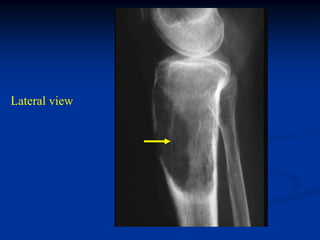

Lateral view

Lateral view showing

path fracture